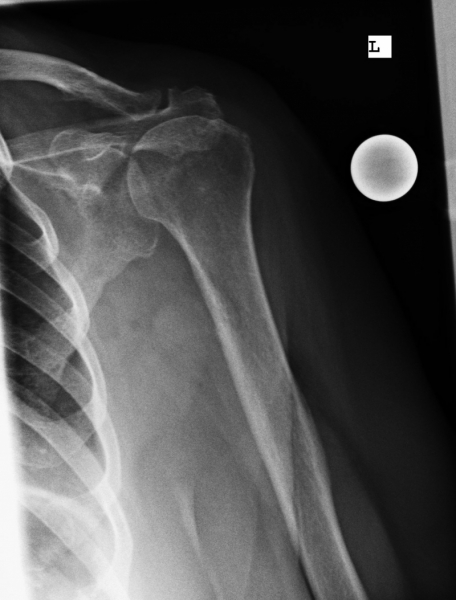

Beispiel einer Inversen Prothese